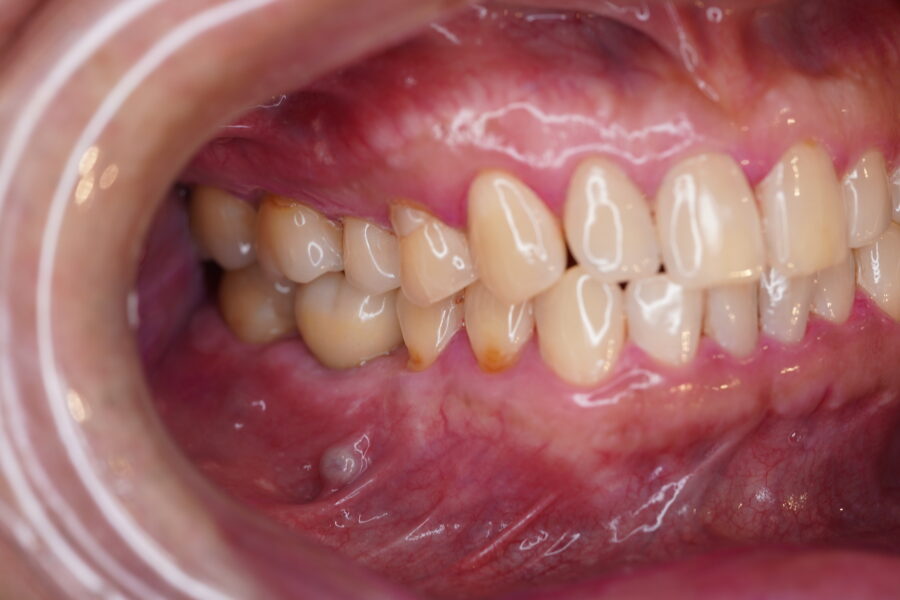

染めだし後のお写真です

もともとクリーニング状態は良好で歯石は付いていませんでしたが、このように染めだすとところどころプラークと言われる見ただけではわからない汚れが見られました